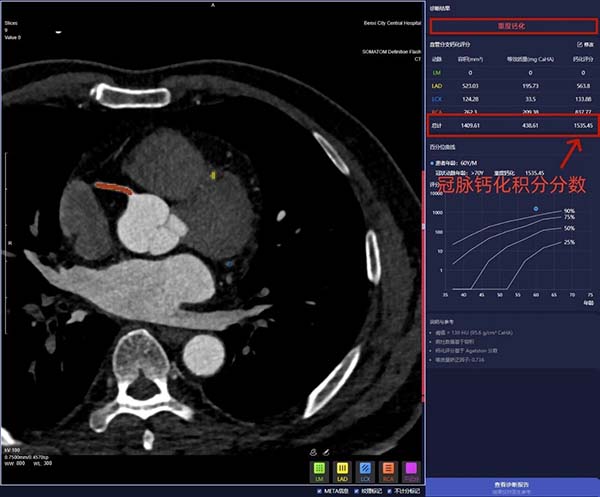

冠状动脉钙化积分>1500,提示极重度钙化

报告上的分数直接对应风险,记好这几个数,自己也能判断:

0分:血管里没发现明显钙化,血管状态不错,继续保持健康习惯就好;

1—10分:轻微钙化,低风险,定期复查,少吃重油重盐、多运动;

11—100分:中度钙化,中低风险,重点控制血压血脂,必要时咨询医生;

101—300分:重度钙化,中高风险,需警惕冠心病、心肌梗死,听医生安排进一步检查治疗;

≥300:极重度钙化,高风险,血管可能已经严重狭窄,赶紧就医评估。